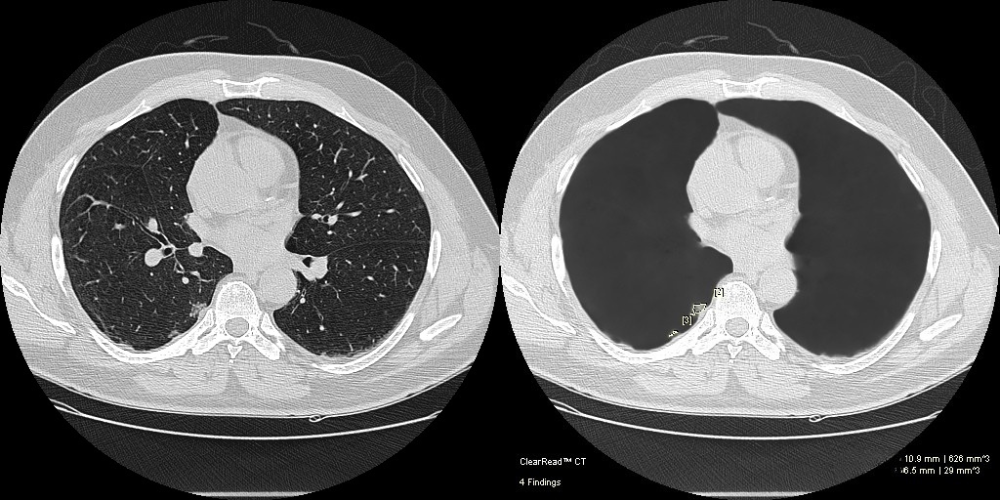

- Exclusive vessel suppression capability provides an unimpaired view of the chest and is approved for concurrent reading

Pulmonary Nodules Automated nodule analysis, current and prior, and reporting to lighten cognitive load

- Fully-automatic nodule detection and analysis